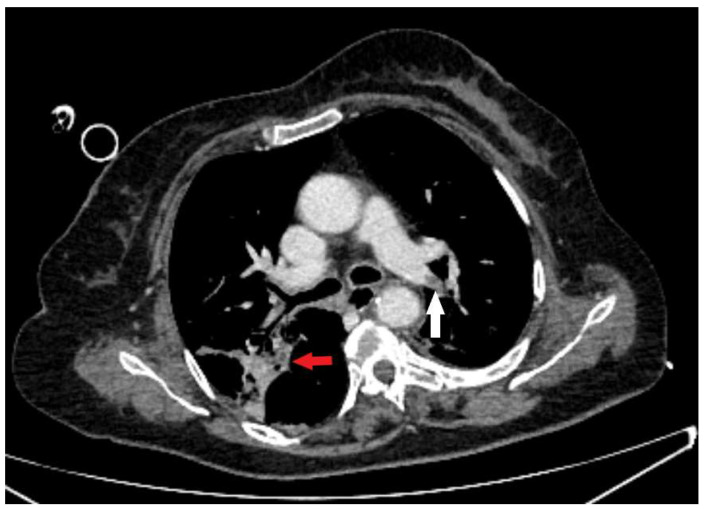

气消化瘘管是临床实践中的一个主要挑战。尽管最近内镜腔内修复技术有了很大的优势,但这个问题的发病率和死亡率都很高。特殊的问题是瘘管局部较高,累及食管和气管近端,这在成人中最常由插管后损伤引起。手术通常要求很高,而且是为那些其他侵入性较小的选择失败的患者保留的。在此,我们报告一例插管后气管食管瘘,经内镜血管塞置入成功治疗。

Aerodigestive fistulas represent a major challenge in clinical practice. This problem is burdened with severe morbidity and mortality, despite recent advantages in endoscopic endoluminal repair techniques. Special problems are fistulas localized higher, engaging the proximal esophagus and trachea, which in adults most often result from post-intubation injury. Surgery is generally demanding and reserved for the patients in whom other, less invasive options fail. Hereby, we present a case of post-intubation tracheoesophageal fistula, successfully treated with endoscopic vascular plug placement.